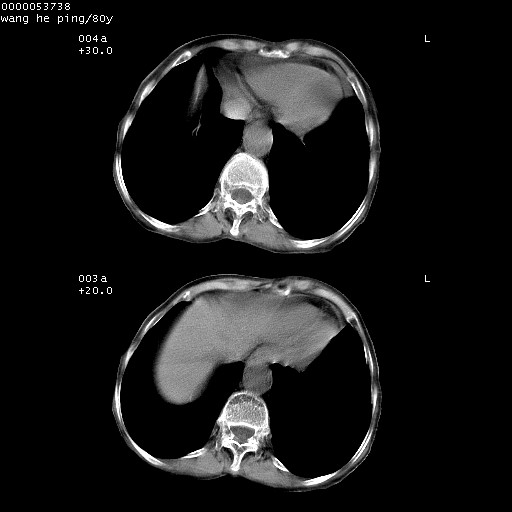

以下是引用lshx在2008-8-28 22:06:00的发言:[br]1.右肺中心型肺癌伴阻塞性肺炎,不除外双 肺早期转移。[br]2.心包积液。

以下是引用随光逐影在2008-8-29 7:40:00的发言:[br]1)右肺中心型肺癌伴阻塞性肺炎,肺内转移。2)心包积液(少量)。

以下是引用wqs571018在2008-8-28 21:56:00的发言:[br]右肺中心型肺癌伴阻塞性肺炎可能。

以下是引用liuyue在2008-8-28 22:46:00的发言:[br]1.右肺中心型肺癌伴阻塞性肺炎。[br]2.心包积液(少量)。